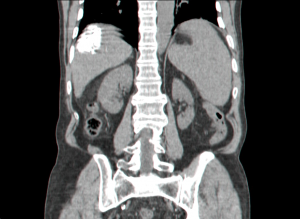

במעבדה ניתן למצוא פוספטאזה בסיסית ו- CEA מוגברים. האבחנה נעשית בעזרת CT, אולטרה-סאונד של הכבד, מיפוי כבד, PET-CT וניקור הכבד. שיטה נוספת היא לפרוסקופיה וניקור ישיר דרך הלפרוסקופ או בעזרת האולטרה-סאונד הלפרוסקופי.

השיטות לאבחון גרורות בכבד הן: אולטראסאונד שבהכוונתו ניתן לבצע ניקור של הכבד ואבחנה של מהות הגוש. CT היא בדיקת הבחירה להדגמת גרורות בכבד ובהכוונתה ניתן לדגום את הגרורות (תצלום 37.10).

| תצלום 37.10: גרורות מרובות בכבד הנראות ב- CT (חץ). | |

|---|---|